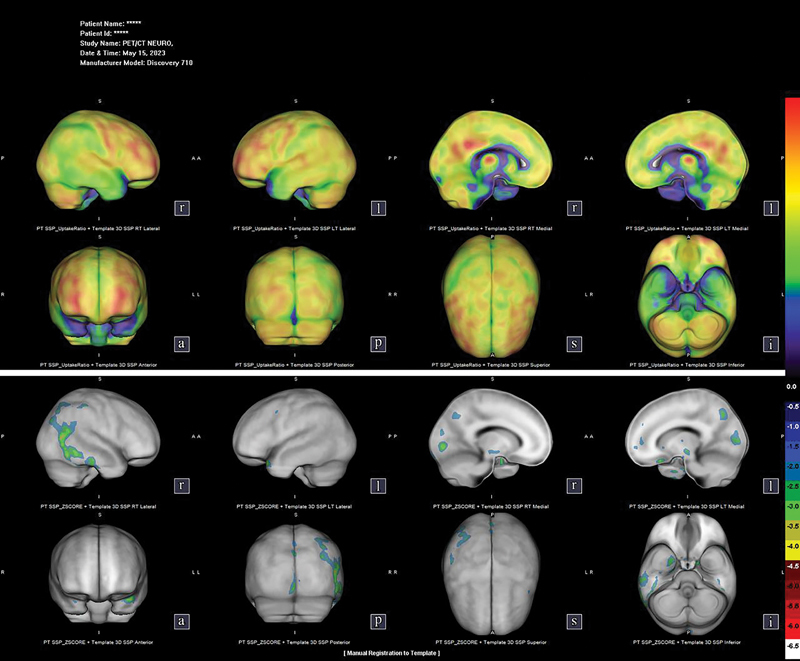

Abstract Image